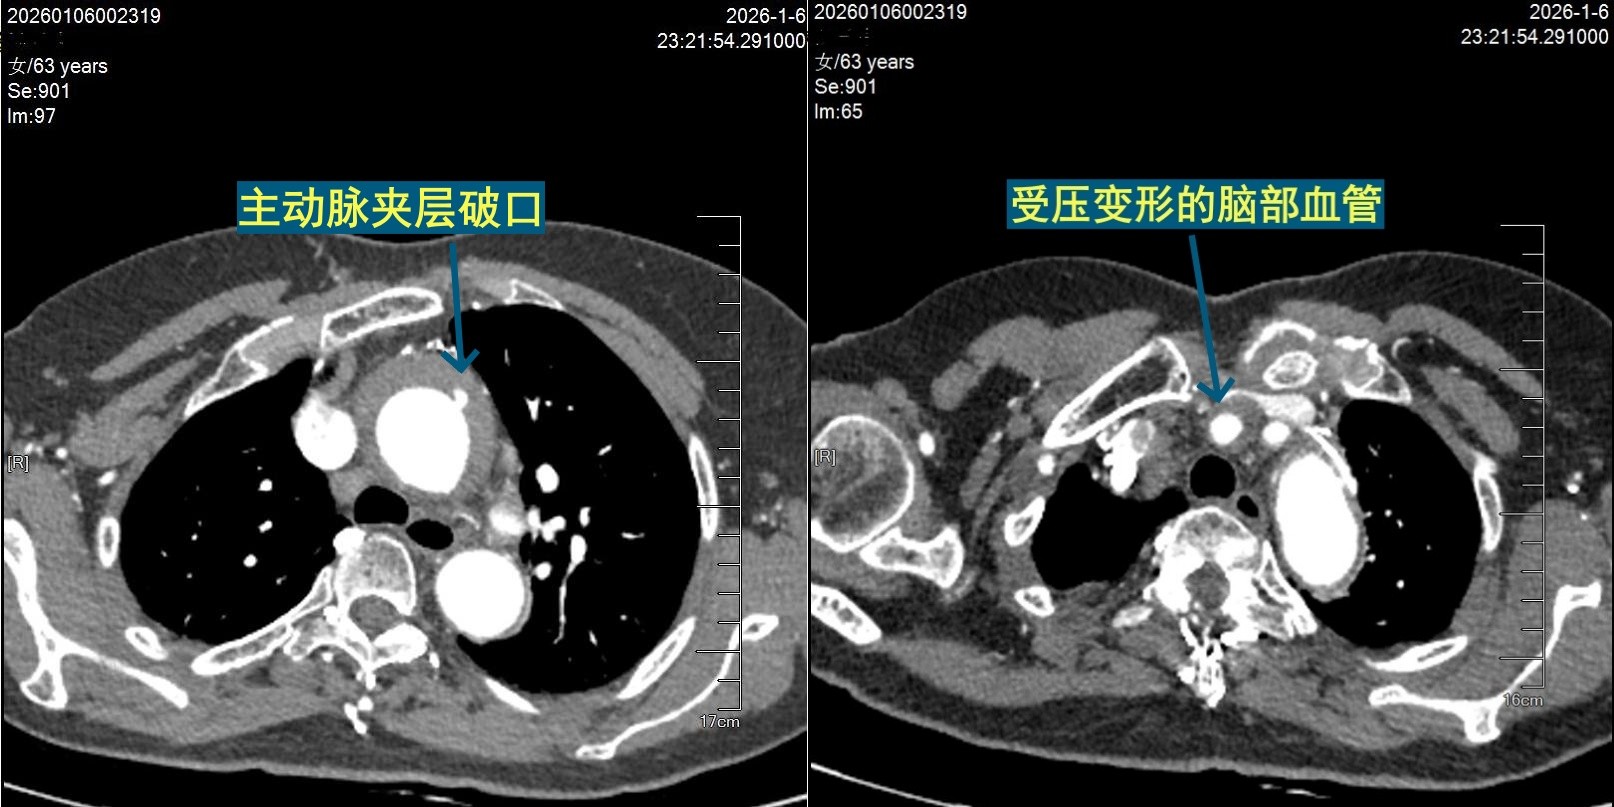

其中A 型主动脉夹层是最凶险的类型,因为它紧邻心脏,血流压力极大,随时可能导致血管破裂大出血,造成急性心包压塞,瞬间致命。数据显示,未及时治疗的 A 型主动脉夹层,每小时死亡率增加 1%,48小时内死亡率高达50%,两周后更是飙升至75%。更棘手的是,汤奶奶的夹层已经严重压迫脑部供血血管,导致急性脑梗死和偏瘫,属于“器官缺血+广泛病变” 的高危情况,手术死亡率极高(A型夹层全球手术院内死亡率约5%-29%,汤奶奶这类术前灌注不良者死亡率更高),而非手术治疗则意味着必死无疑。

(图片2:术前CTA脑部血管受压)

急诊术中发现,汤奶奶的主动脉内膜破口位于升主动脉,夹层病变广泛,给脑部供血的无名动脉真腔被血肿压扁——这正是她偏瘫的根源。潘禹辰团队采用国际标准的“孙氏手术”,先切除病变的主动脉,换上人工血管,在降主动脉植入带覆膜支架,像“支架象鼻” 一样撑开胸降主动脉远端,重建正常血流通道。